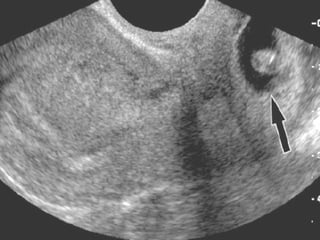

ECOGRAFIA El diagnóstico del EE se ha beneficiado de los avances producidos en el campo de la ecografía, principalmente a través del desarrollo de la vía transvaginal. Varios son los hallazgos ecográficos sugestivos o diagnósticos de EE: - Ausencia de saco intrauterino: un título de b-HCG superior a 1000-1500 UI/l sin saco intrauterino es compatible con EE. Con gestaciones múltiples, el saco gestacional no es visible hasta que los títulos son ligeramente mayores. Por otra parte, la comprobación de un embarazo intrauterino viable no permite descartar por completo la existencia de un EE, debiendo descartar un embarazo heterotópico especialmente cuando se han empleado técnicas de reproducción asistida.

-  Masa anexial anormal que puede  presentarse ecográficamente de diferentes formas: § Saco gestacional típico: corona ecogénica que delimita centralmente una laguna anecoica. § Actividad cardiaca anexial factible cuando los niveles de b-HCG son de aproximadamente 15000-20000 U/l. § Hematosalpinx, aisladamente o asociado al saco gestacional. § Hemoperitoneo, infrecuente cuando el diagnóstico se establece de forma precoz.

¿Que tipo de ecografía?  La ecografía  transvaginal antecede en una semana a la ecografía abdominal en la detección de una gestación intrauterina. La ecografía  transvaginal detecta las masas anexiales mejor que la ecografía abdominal.

Saco seudogestacional  de embarazo ectópico y embarazo temprano intrauterino normal (EIU)